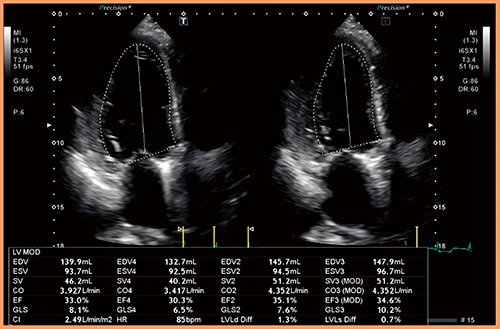

Auto EF計測は,2D WMTのトラッキング手法を応用し,ワンタッチ操作で自動計測を行う。計測結果にはBi-Plane Disk法のEFだけでなく,心筋ストレインの指標となるGlobal Longitudinal Strain値も同時に出力されるため,ルーチン検査での心機能評価をすばやく簡単に行うことができる(図6)。

図6 Auto EF計測による左室機能評価